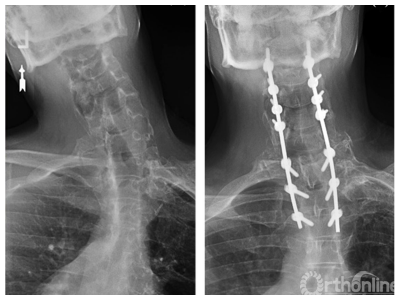

2017年Theologis等报道一例颈部冠状面畸形的患者,采用非对称C7 PSO进行矫正。非对称C7PSO 操作过程与C7PSO类似,不同之处在于凸侧的截骨量多于凹侧。该术式适用于颈胸段冠状面畸形的矫正。

1. Theologis AA, et al. Asymmetric C7 pedicle subtraction osteotomy for correction of rigid cervical coronal imbalance secondary to post-traumatic heterotopic ossification: A case report, description of a novel surgical technique, and literature review [J]. Eur Spine J, 2017, 26(1): 141-145.